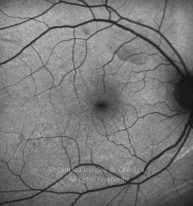

Paciente de 37 años con traumatismo contundente y ruptura del globo ocular. Presenta ruptura esclero-uveal, hifema, hemovítreo, desgarro periférico y temporal de la retina, hemorragias subretinianas y múltiples desprendimientos serosos.

MAVC: 20/25 OD, nueve años después de las cirugías (sutura escleral de la desinserción del músculo recto externo, vitrectomía posterior y fotocoagulación láser en el borde del desgarro retiniano, desprendimiento de retina inferior con proliferación vitreorretiniana y líquido subretiniano con algo de sangre; peeling de la membrana epirretiniana y maculorrexis de la MLI).